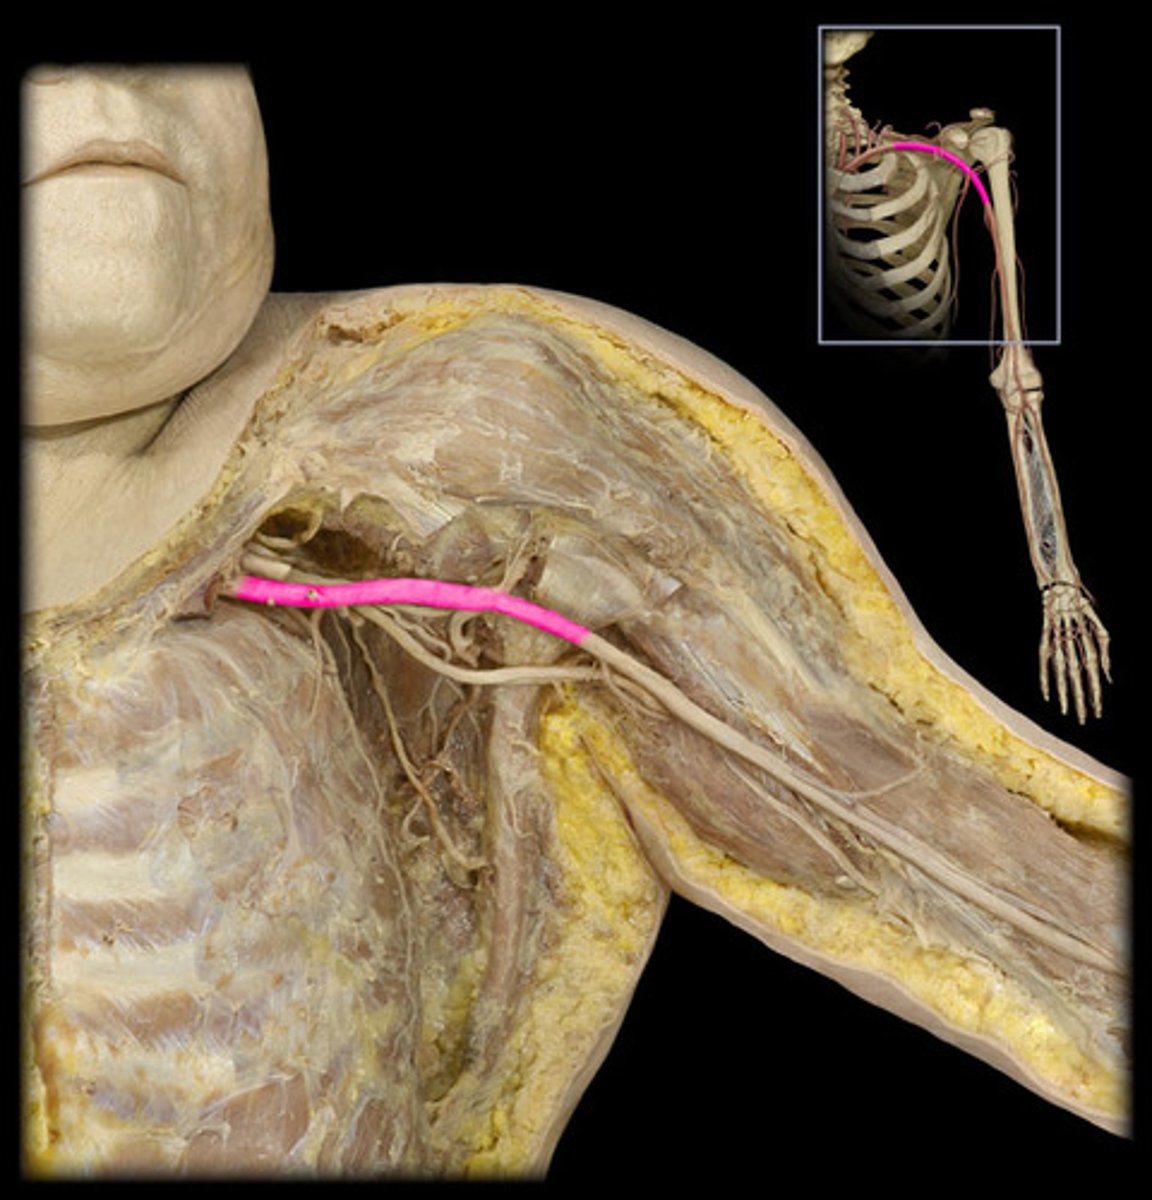

Axillary a.

armpit

Brachial a.

Name this structure.